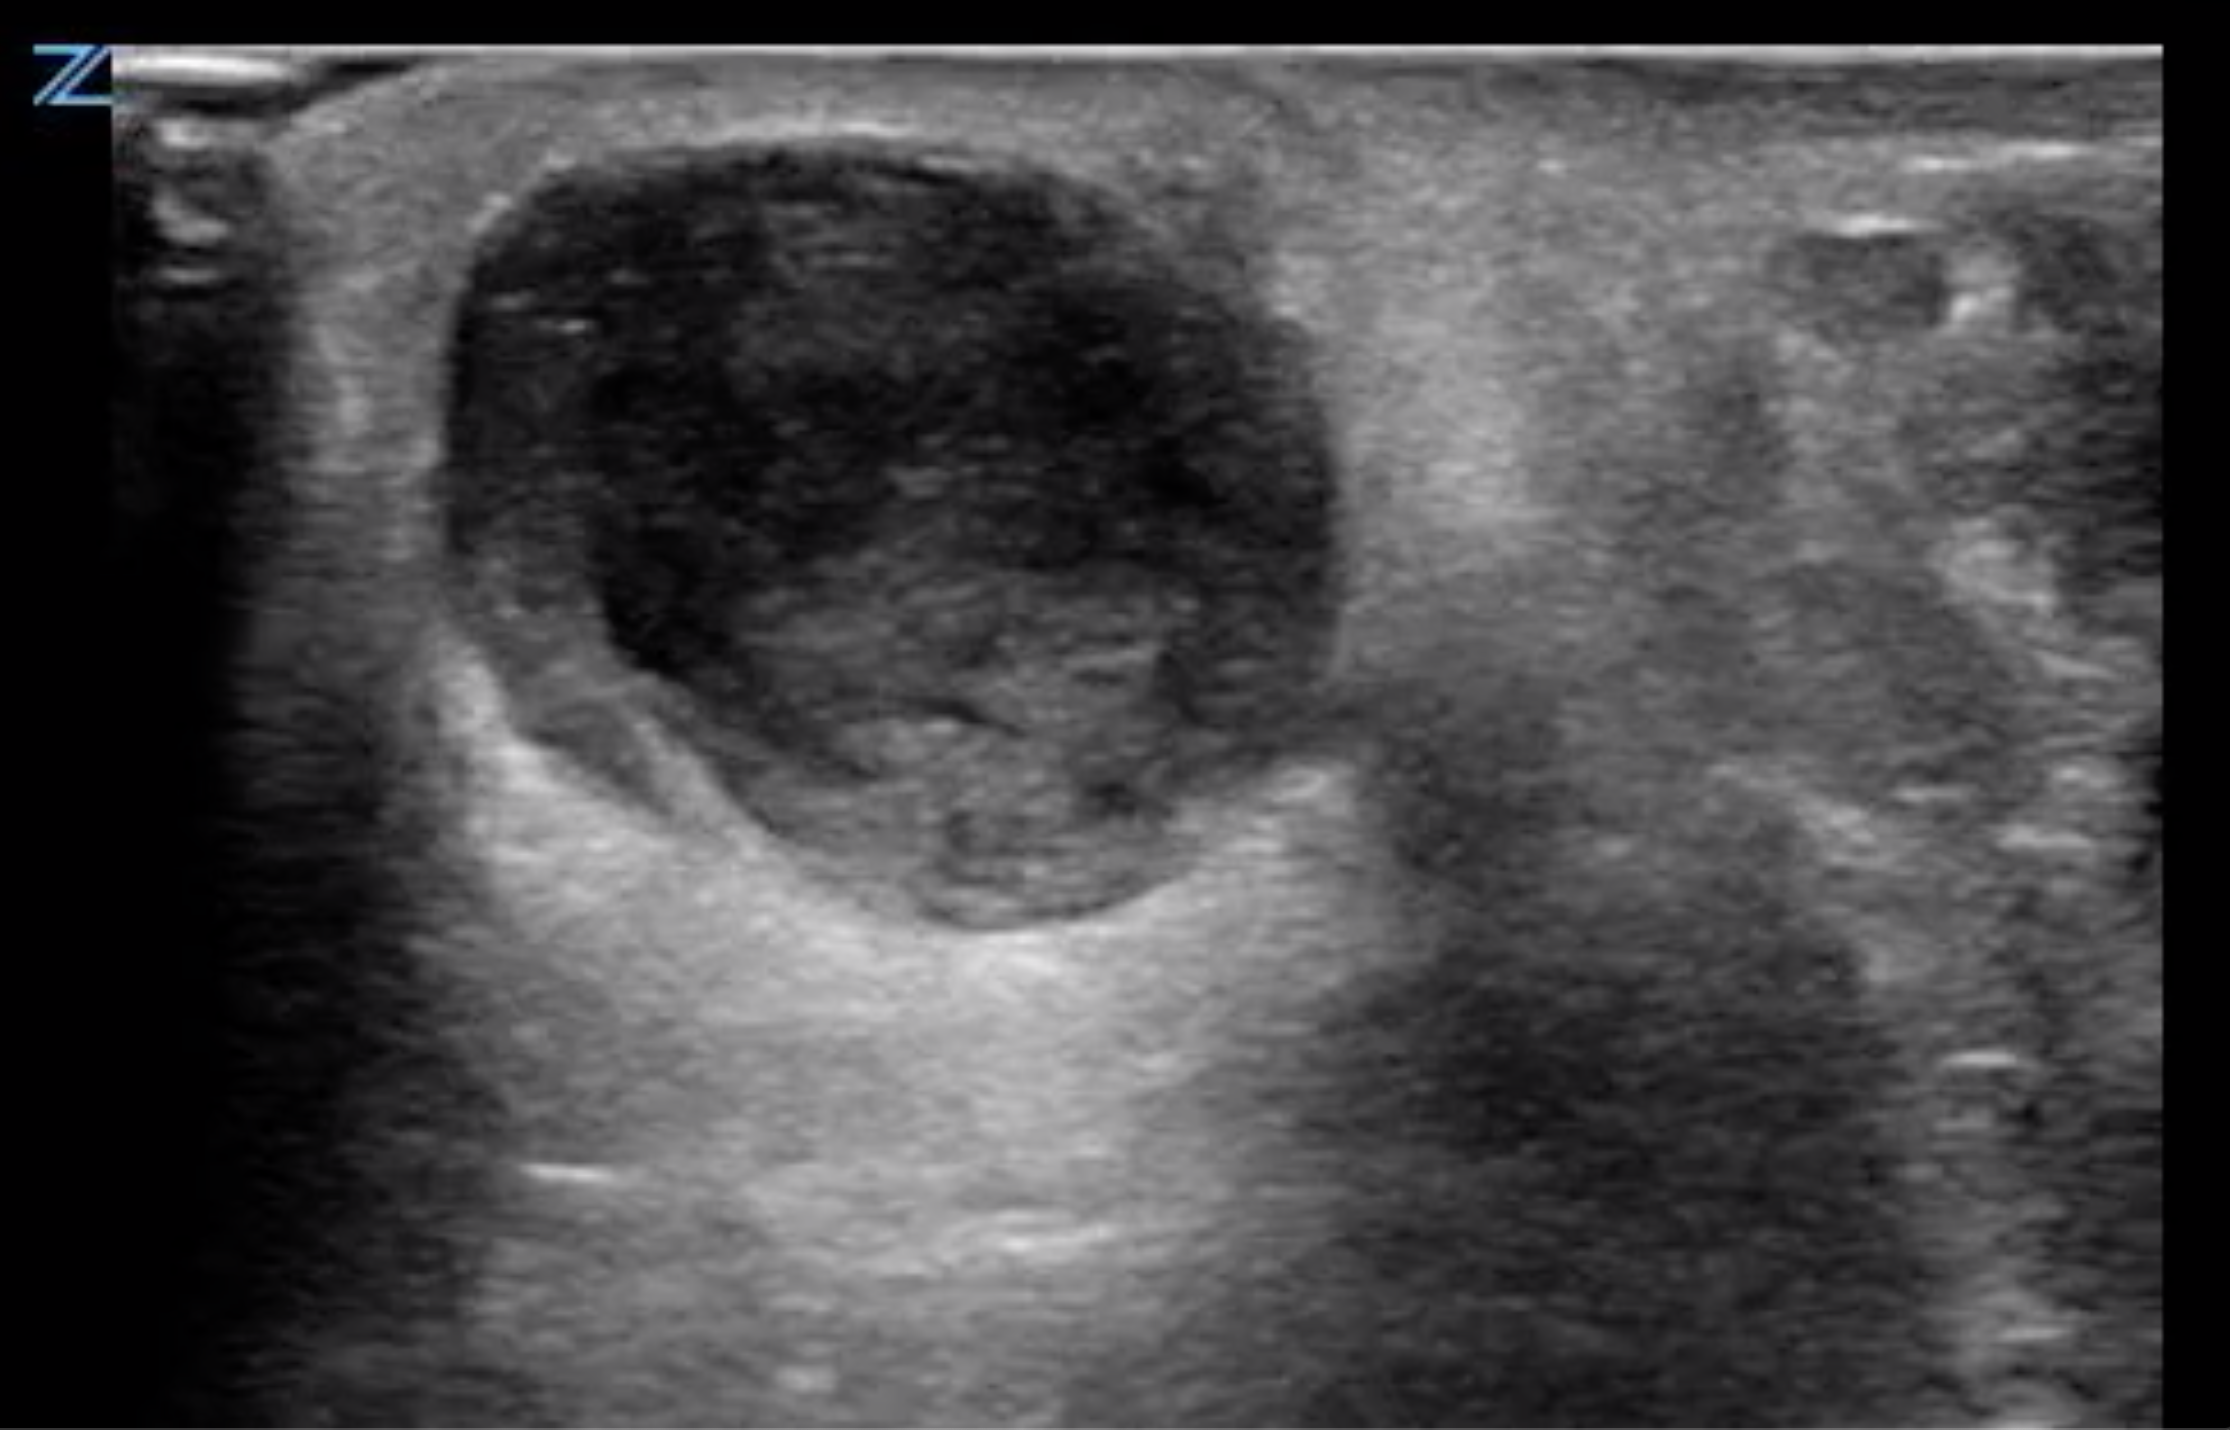

- Figure 2. Abscess containing hyperechoic debris

- On ultrasound, an abscess is a spherical or oblong structure that is largely anechoic or hypoechoic.

- However, as opposed to a simple cyst that will be uniformly anechoic throughout, an abscess will contain hyperechoic debris. This feature can be used to differentiate an abscess from a cyst.

- The walls of the abscess cavity might be distinct and hyperechoic, or they might have a ragged appearance and intermix with the adjacent tissue. Because of the anechoic nature of the abscess, posterior acoustic enhancement might be seen.

- Dynamic scanning, achieved with gentle compression of the probe, might cause the contents of the abscess to swirl, which can be diagnostic of an abscess.

- On ultrasound imaging, an abscess appears as a spherical or oblong anechoic or hypoechoic collection containing hyperechoic debris.